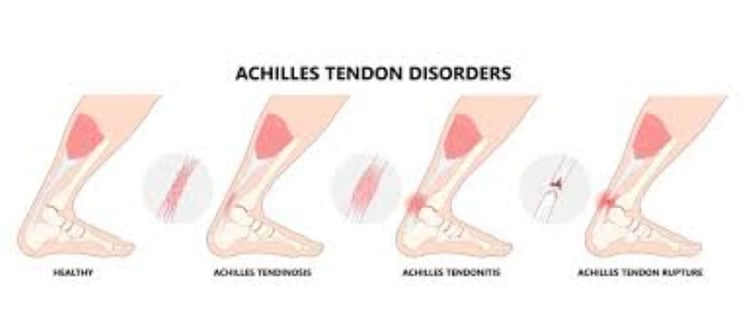

التهاب وتر أخيل (Tendinitis/Tendinosis):

الوصف: حالة ناتجة عن الإجهاد المستمر أو المتكرر، تتميز بتمزقات دقيقة وضعف في الوتر (طب العظام السريري، 2022).

التهابي قصير الأمد (Tendinitis): يتضمن التهابًا حادًا (دراسات الالتهاب، 2023).

تنكسي طويل الأمد (Tendinosis): يشمل تحلل الخلايا وفقدان الكولاجين (مجلة التنكس العضلي، 2022).

غير ارتكازي (Noninsertional): يصيب الجزء الأوسط من الوتر (2-6 سم فوق العقب)، وهي "نقطة ضعف الأوعية الدموية" بسبب قلة التروية الدموية (علم الأوعية، 2023).

ارتكازي (Insertional): يصيب المنطقة السفلية عند الارتكاز بعظم الكعب، غالبًا مع نتوءات عظمية (دراسات العقب، 2022).

تمزق وتر أخيل:

الوصف: تمزق جزئي أو كامل، يحدث غالبًا أثناء الأنشطة الرياضية مثل الجري السريع أو القفز (مجلة الصدمات، 2023).